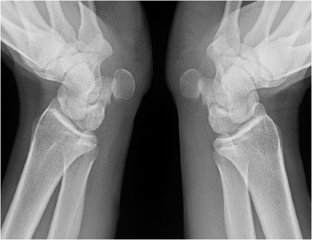

Fig. 4